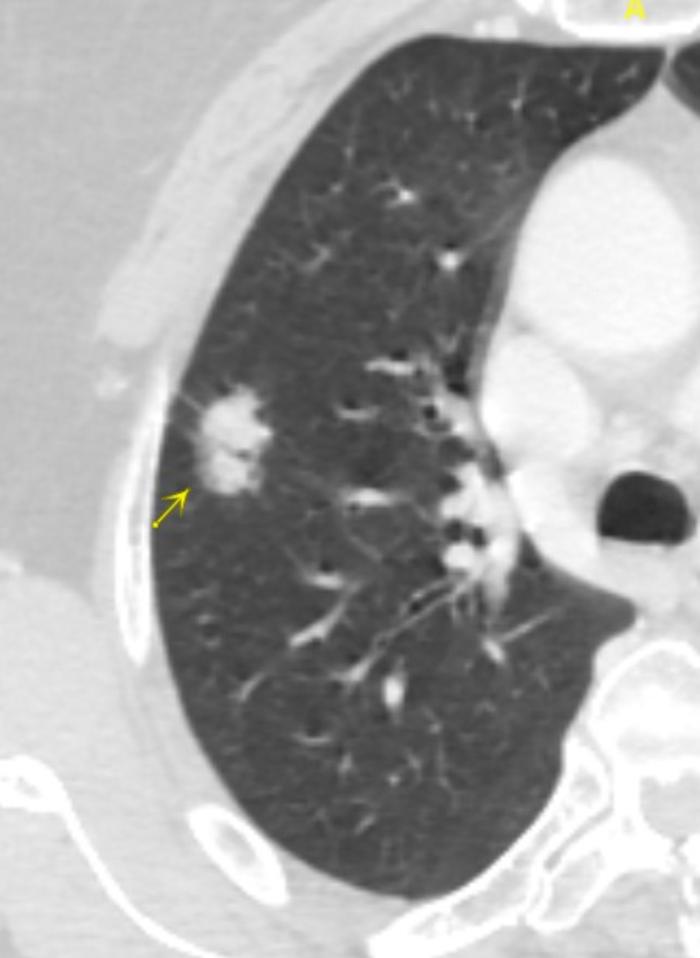

病例八、囊腔性腺癌。

这是一个左上肺的混合磨玻璃结节。特点是一个比较大的囊腔,周边或内部有磨玻璃成分,注意不要和肺大疱混淆。这个结节有30毫米大,4个箭头指示的是结节的内侧和后侧有大约3-5毫米厚的磨玻璃成分。一看就是一个典型的囊腔性腺癌。